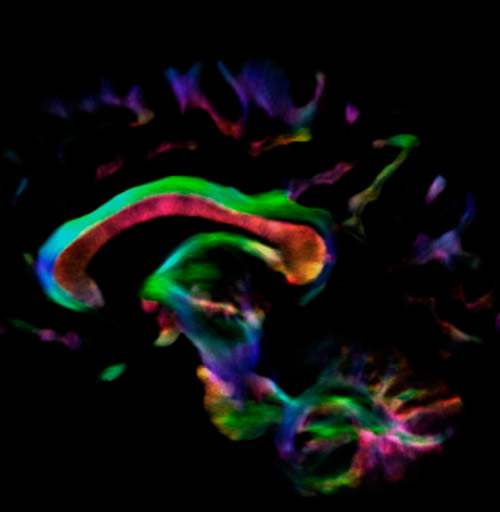

All images were created from the same acquisition in a child using Ingenia 3.0T CX and 32-channel dS Head coil. Diffusion data was acquired at b-values 0, 500, 1000, 2000, 3000. The use of high b-values (3000 s/mm2) effectively suppresses extra-axonal water signal and provides high angular resolution.

Fiber tracking based on CSD analysis of multishell DWI data and probabilistic tractography.

Fiber tracking from the left and right hippocampi to the fornix.

Fiber tracking from the left and right hippocampi to the fornix (green), and the corticospinal track based on a seed region of the posterior limb of the internal capsule.